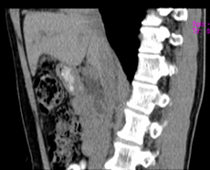

患者,男,57,常年不吃午饭,近一个月来腹部隐痛,无明显黄疸,明天进行增强扫描,图象另上传,麻烦各位帮忙一起看看讨论讨论

肝外胆管扩张,胰头增大,肠系膜上静脉似有包埋征象。

考虑:胰头占位性病变,建议增强进一步检查。

肝外胆管稍扩张,胰腺钩突略增大,但外形尚可,境界清楚。(常年不吃午饭)提示胰腺炎可能大,肿瘤第二步考虑。

支持考胰头占位性病变,感觉十二指肠壁不规则增厚,不排除十二指肠降部占位可炎症

胰头增大,胆总管增宽,考虑胰头癌可能性大,明天看增强片有助诊断.